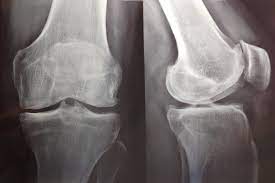

Restauración del ensayo PRGF: un ensayo clínico aleatorizado en plasma rico en factores de crecimiento para la artrosis de rodilla

este nuevo análisis del estudio PRGF no encontró ningún beneficio clínica o estadísticamente significativo del plasma rico en factores de crecimiento (PRGF) en comparación con el ácido hialurónico. La restauración del Estudio PRGF muestra la urgencia de cambios importantes en las prácticas de supervisión e informes de juicios. En el futuro, se necesita acceso oportuno a todos los documentos de ensayos clínicos para minimizar el riesgo de sesgo de informe. Del mismo modo, los comités de ética deben estar listos para intervenir cada vez que surja un caso de posible mala conducta. Trials, 18 de enero de 2023